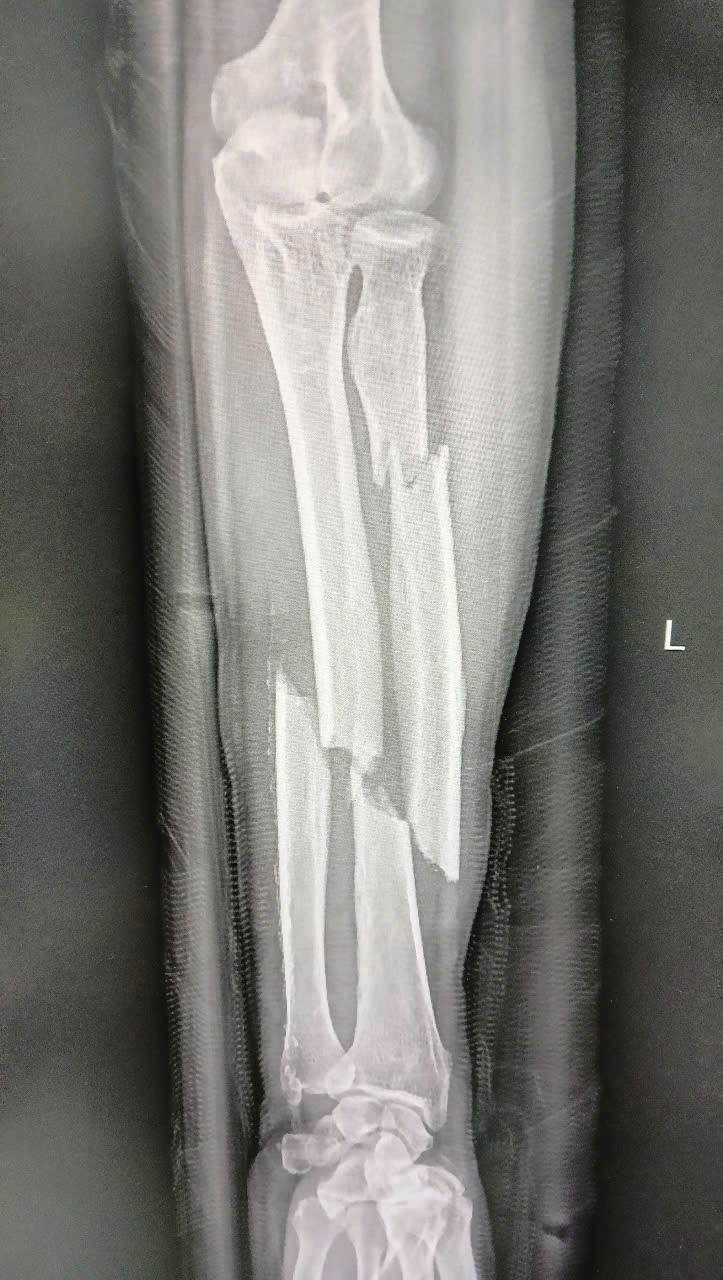

- Sử dụng các kỹ thuật chụp X-quang, CT scanner.. để đánh giá chi tiết tình trạng gãy xương.

- Người bệnh T.V.H (65 tuổi): Bị gãy hở xương quay và xương trụ do tai nạn giao thông nghiêm trọng, kèm tổn thương nội sọ và vết thương lóc da bàn tay.

- Phương pháp xử lý: Phẫu thuật kết hợp xương bởi đội ngũ Bác sĩ chuyên gia Chấn thương Chỉnh hình với kỹ thuật hiện đại. Sau phẫu thuật, người bệnh được chăm sóc và phục hồi nhanh chóng, có thể vận động cổ tay nhẹ nhàng, không còn cảm giác đau đớn